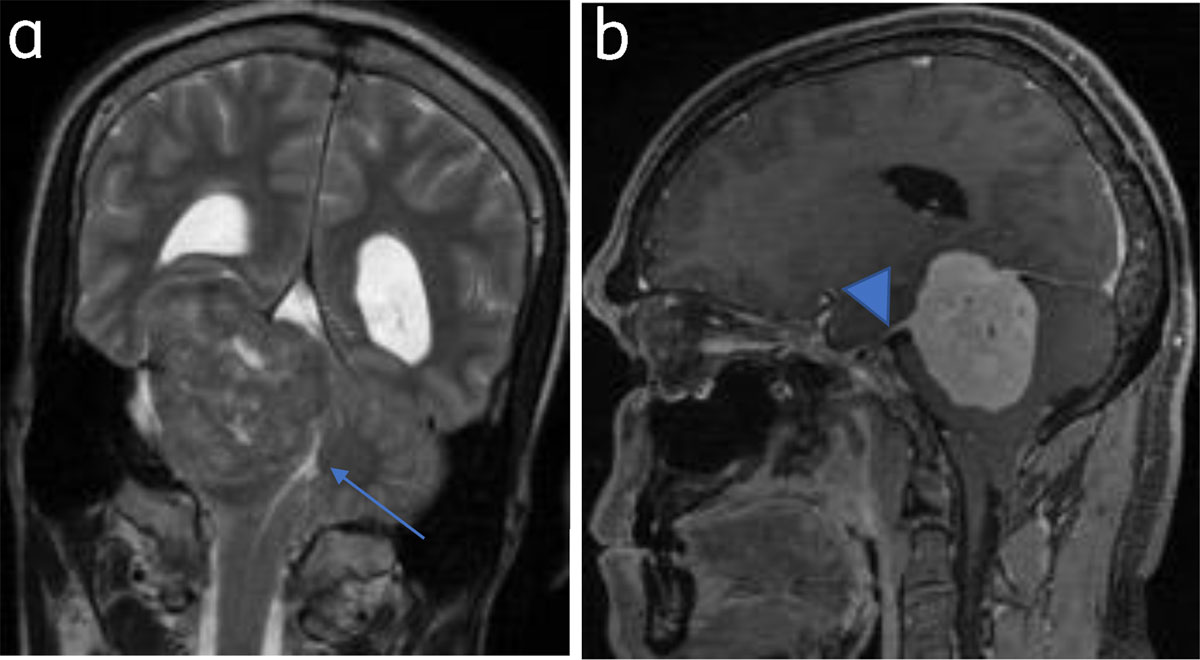

“Dural tail sign” refers to focal (linear or patchy) dural enhancement adjacent to the tumor and can be extensive. Can also be seen in metastases, lymphomas, and some glial tumors [4] (Figure 2).

Figure 2

Tentorial meningioma with dural tail: (a) Coronal T2WI tentorial meningioma. Fourth ventricle is effaced (arrow). (b) Sagittal post contrast image shows dural tail (arrowhead).